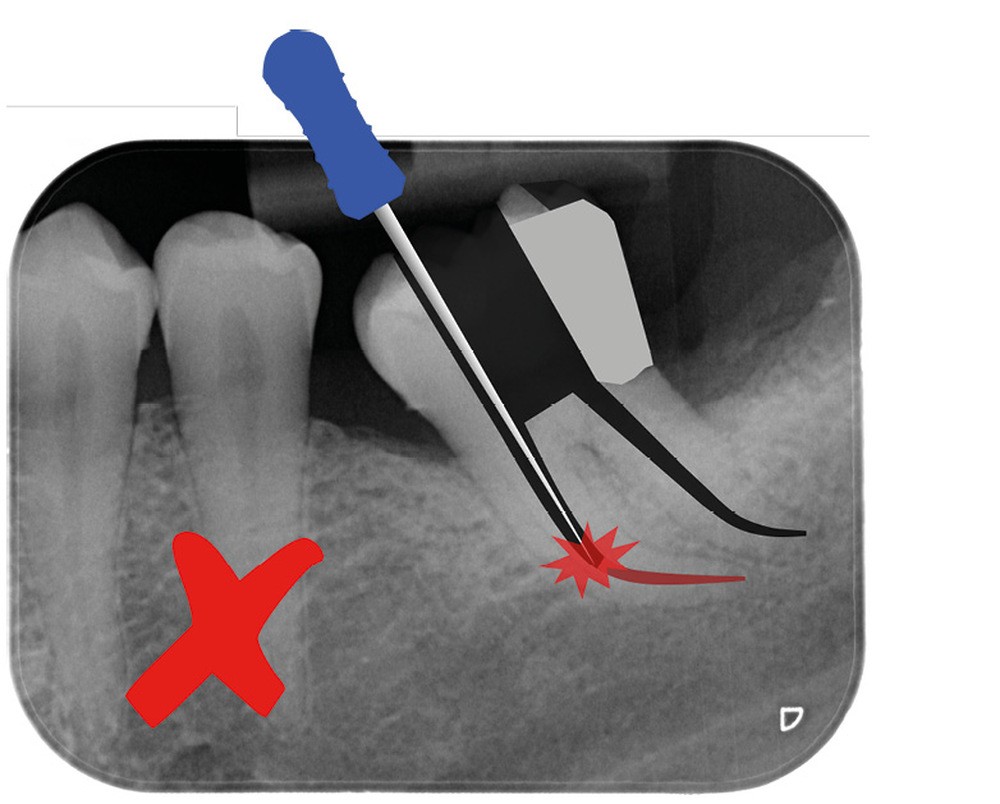

Une cavité d’accès trop petite [2] optimiserait le pronostic biomécanique (préservation dentaire maximale) mais pourrait compromettre le pronostic endodontique : mauvaise lecture de l’anatomie, instrumentation partielle, non ergonomique et avec risque de fracture, défaut de nettoyage des parois canalaires [3], irrigation inadéquate, difficulté d’obturation canalaire, voire d’obturation coronaire. Ce sera le cas des cavités d’accès « Ninja » [4] ou ultraconservatrice (fig. 1), des cavités d’accès « Truss » [5] (fig. 2), des cavités d’accès dites « opportunistes » [6] (fig. 3).

Trop petite